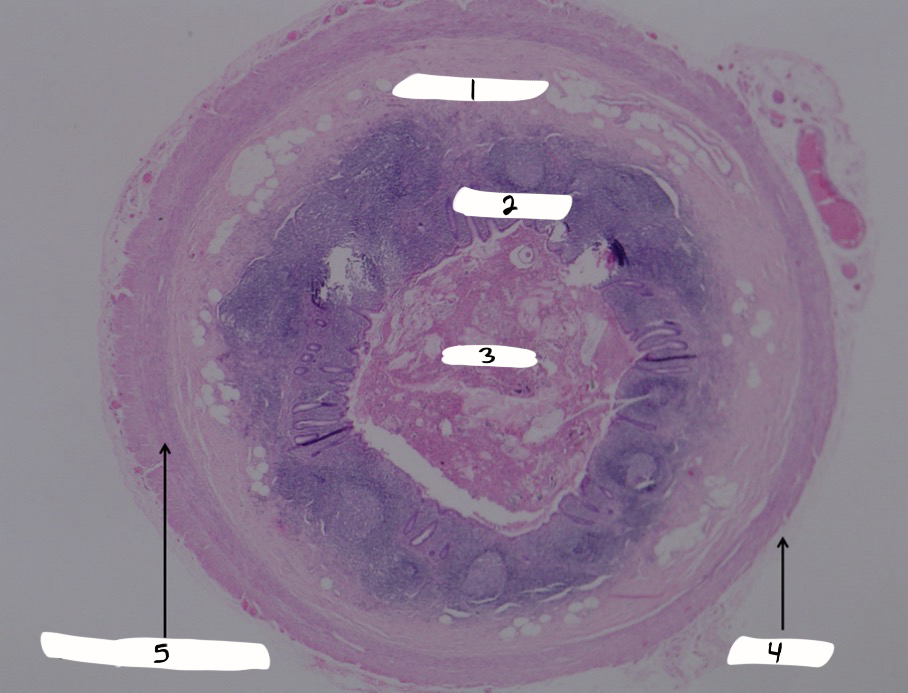

blood vessels

what is this a sample of?

artery

what is #1?

vein

what is #2?

lumen

what is #3?

tunica intima

what is #4?

tunica media

what is #5?

tunica externa

what is #6?